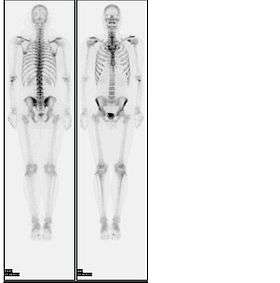

A nuclear medicine whole-body bone scan. The nuclear medicine whole-body bone scan is generally used in evaluations of various bone-related pathology, such as for bone pain, stress fracture, nonmalignant bone lesions, bone infections, or the spread of cancer to the bone.

Bone scan showing multiple bone metastases from prostate cancer.